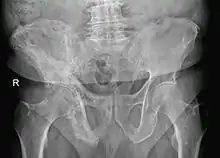

- Pagetic bone has a characteristic appearance on X-rays. A skeletal survey is therefore indicated.

- Bone scans are useful in determining the extent and activity of the condition. If a bone scan suggests Paget's disease, the affected bone(s) should be X-rayed to confirm the diagnosis.